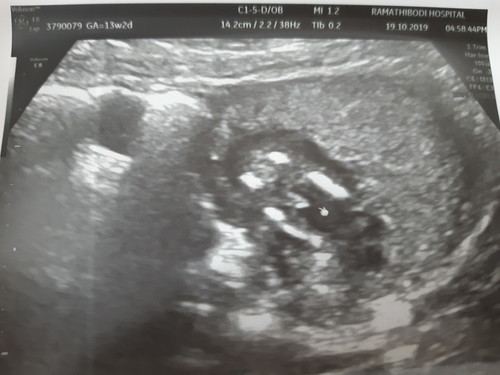

13 w 2 d ...เพศไรกันน้าาาา

หมอบอกว่าแนวโน้มเป็นหนุ่มน้อยค่า แม่ ๆ คิดว่าอย่างไรคะ

ผู้ชายชัวร์ค่ะ